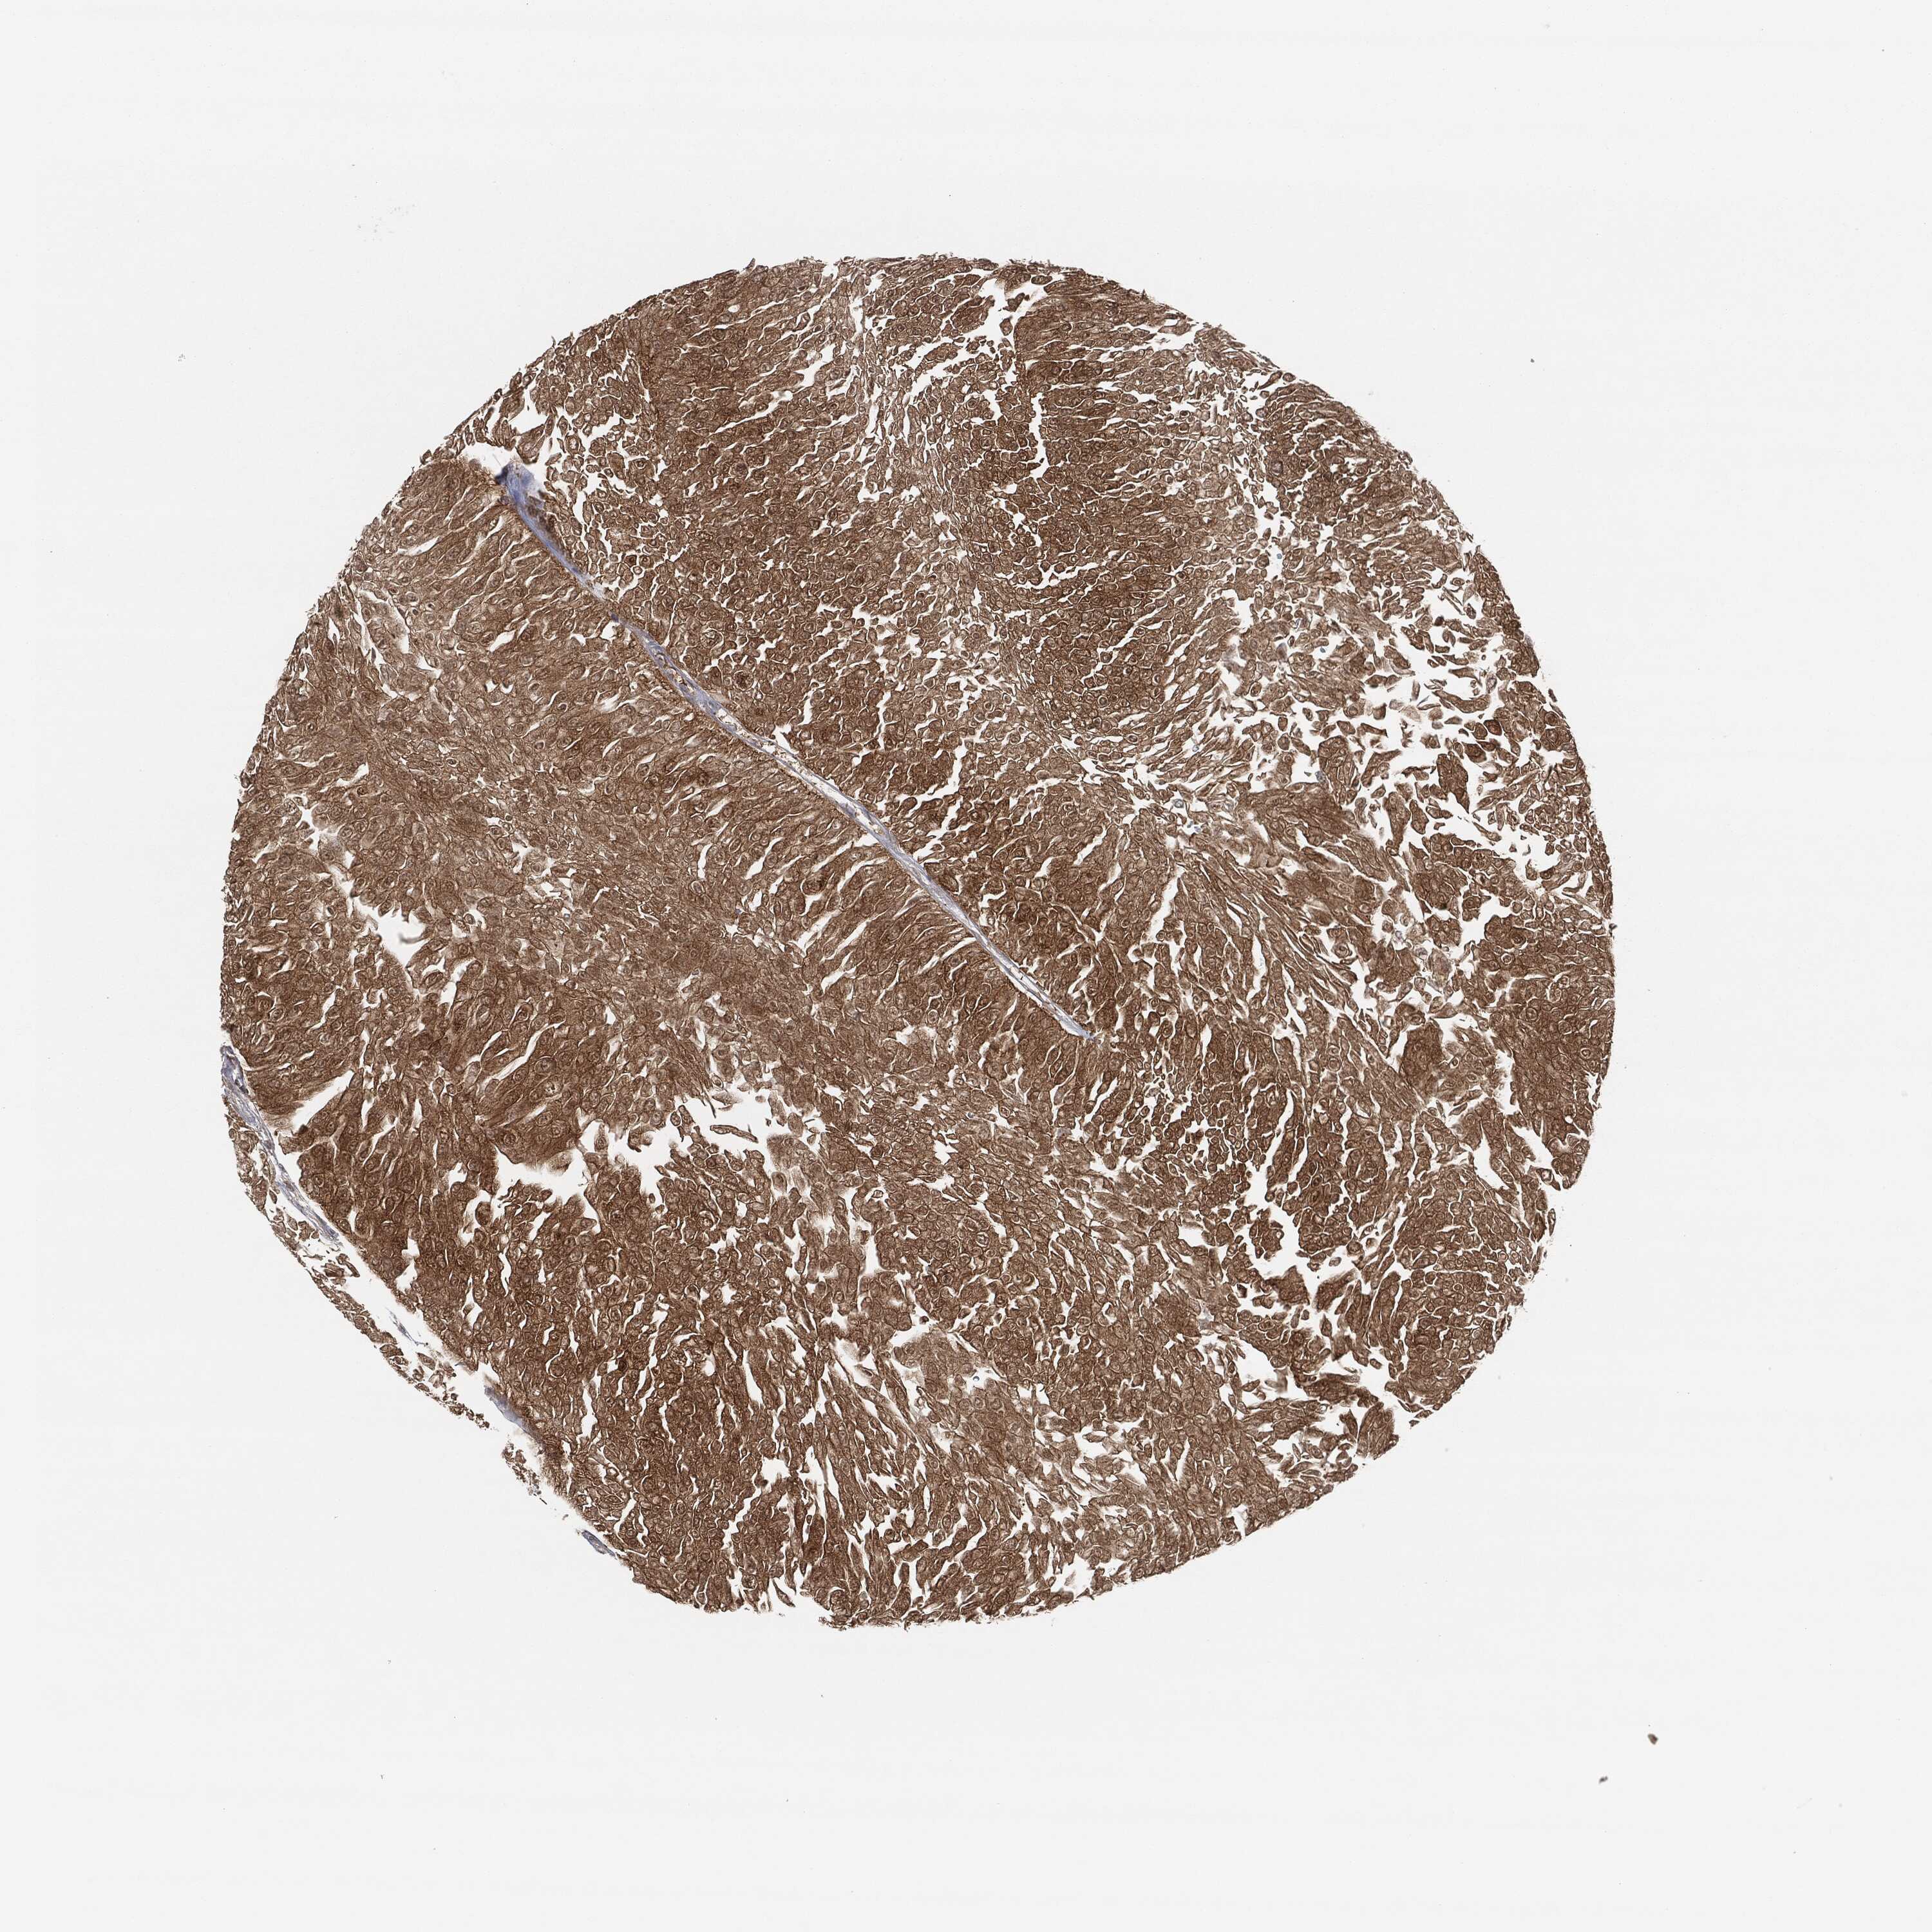

UROTHELIAL CANCER - Protein expressioni

A mouse-over function shows sample information and annotation data. Click on an image to view it in a full screen mode. Samples can be filtered based on level of antibody staining by selecting one or several of the following categories: high, medium, low and not detected. The assay and annotation is described here.

Antibody stainingi

Antibody staining in the annotated cell types in the current human tissue is reported as not detected, low, medium, or high, based on conventional immunohistochemistry profiling in selected tissues. This score is based on the combination of the staining intensity and fraction of stained cells.

Each image is clickable and will lead to virtual microscopy that enables deeper exploration of all samples and also displays staining intensity scores, fraction scores and subcellular localization as well as patient and tissue information for each sample.

Antibody CAB000102

Antibody CAB080442

Staining

High

Medium

Low

Not detected

Intensity

Strong

Moderate

Weak

Negative

Quantity

>75%

75%-25%

<25%

None

Location

Nuclear

Cytoplasmic/membranous

Cytoplasmic/membranous,nuclear

Urothelial carcinoma, High grade

Urothelial carcinoma, Low grade

Adenocarcinoma, NOS